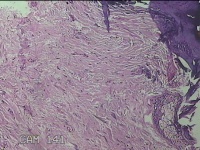

右颈部皮肤肿物

性别

女

年龄

29岁

临床诊断

纤维瘤

一般病史

右颈部皮肤起肿物10年左右。

标本名称

大体所见

灰白暗红色肿物0.3x0.2x0.1cm一个,表面光滑。

图4